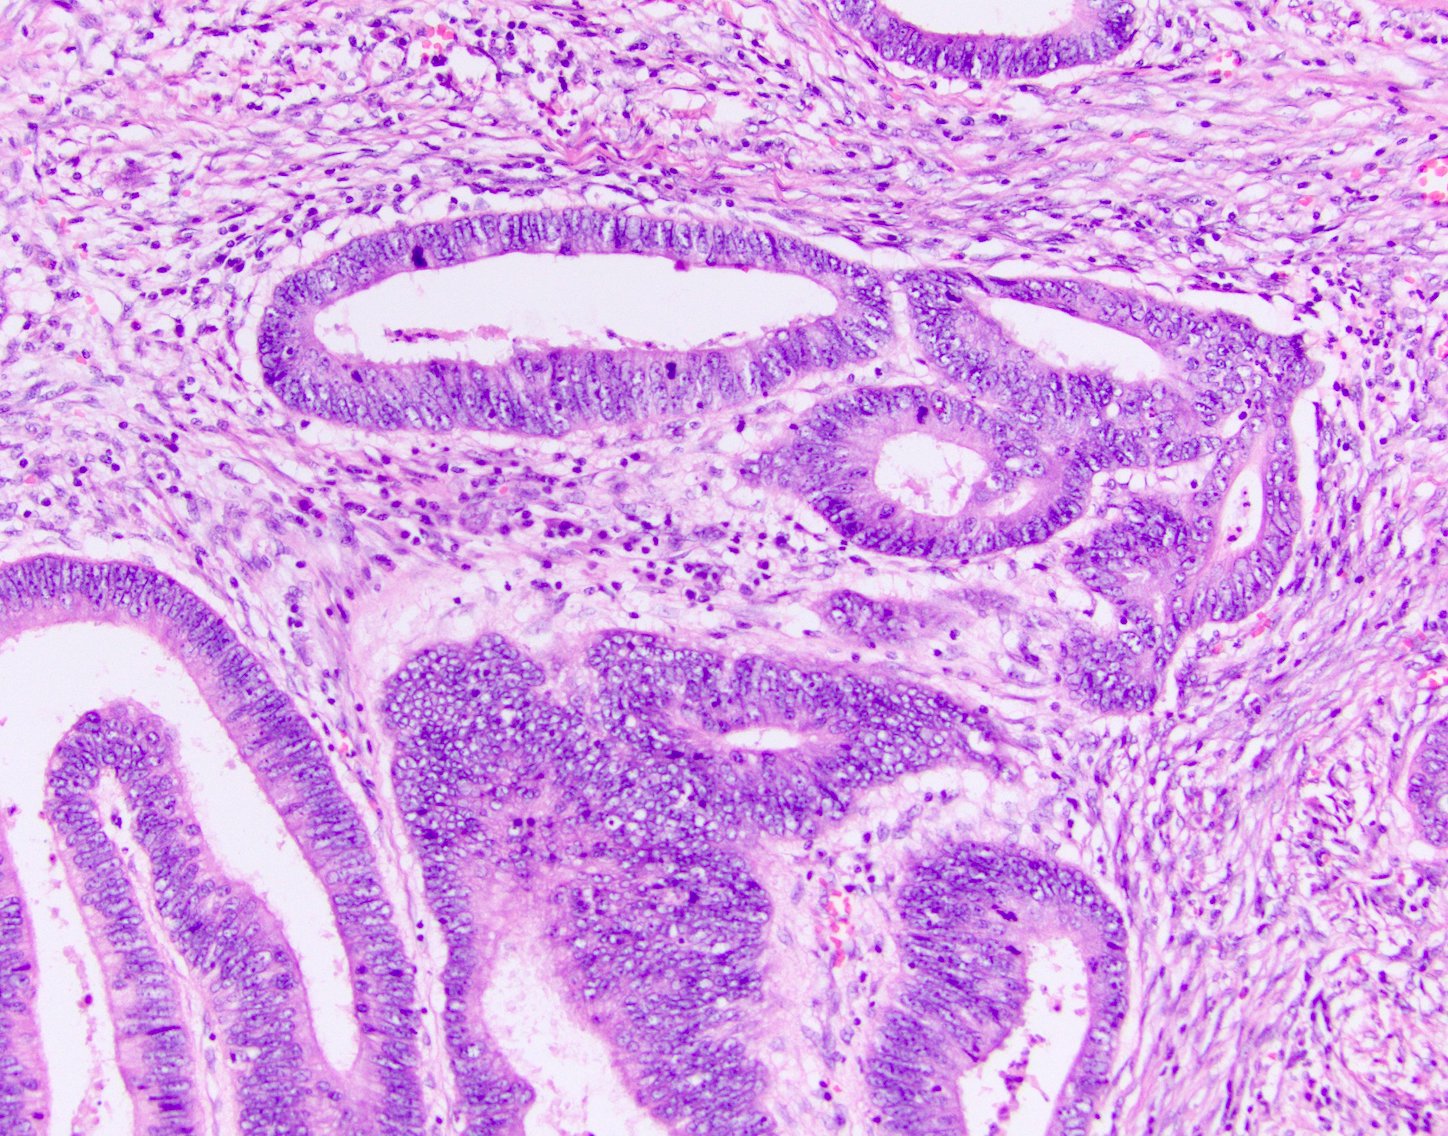

- 1Malignant glandular structures infiltrating stroma

- 2Pleomorphic columnar cells with nuclear hyperchromasia

- 3Intraluminal mucin and necrotic debris

- 4Desmoplastic stromal reaction

Adenocarcinoma is a malignant epithelial tumour showing glandular differentiation. Histologically it features irregular malignant glandular structures lined by pleomorphic columnar cells, abundant intraluminal mucin, infiltration through the muscularis mucosae, desmoplastic stromal reaction, and lymphovascular invasion.

- Irregular, atypical glandular structures — architectural distortion

- Abundant intraluminal mucin (mucinous variant: >50% mucin pools)

- Cancer cells infiltrating through the muscularis mucosae into submucosa

- Lymphocytic and plasma cell infiltration in the stroma

- Desmoplastic stromal reaction around tumour glands